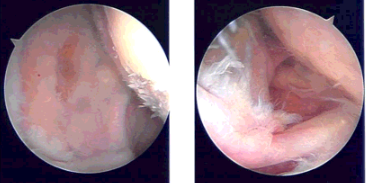

A spinal needle was used to make an anterosuperior portal. Shaver was introduced from the anterosuperior portal. There were grade II to grade III osteoarthritic changes on the glenohumeral joint. There was extensive fraying with a high-grade partial thickness tear of the rotator cuff.

Debridement was done for the glenohumeral joint. After that, the rotator cuff was debrided. The tear was converted into a full thickness tear easily. The biceps were intact. There was synovitis, which was also debrided.

The arthroscope was entered from the anterior portal and the shaver from the posterior portal to complete the debridement. There was a loose body in the glenohumeral joint, which was removed. It seemed to be an osteophyte, which was loose. The arthroscope was entered into the subscapularis region.

Pictures were taken. A distal clavicle excision was planned, finding an osteophyte there. A distal clavicle excision was done from the posterior portal following the anterior portal. About a centimeter of distal clavicle was excised. Final pictures were taken and saved.